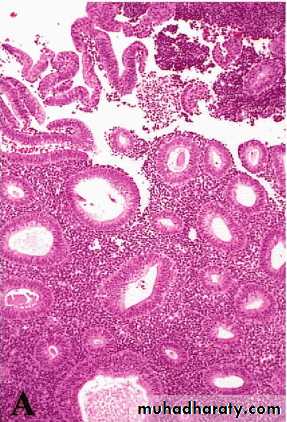

Endometriosis. A, Endometriosis is present in the mucosa of the colon. B, Higher magnification reveals the presence of both endometrial glands and stroma

endometrial glands and stroma invaginated in myometriumEndometriosis

Microscopic featuresThe histologic diagnosis depends on finding two of the following three features within the lesions:

1. Endometrial glands.

2. Endometrial stroma.

3. Hemosiderin pigment.